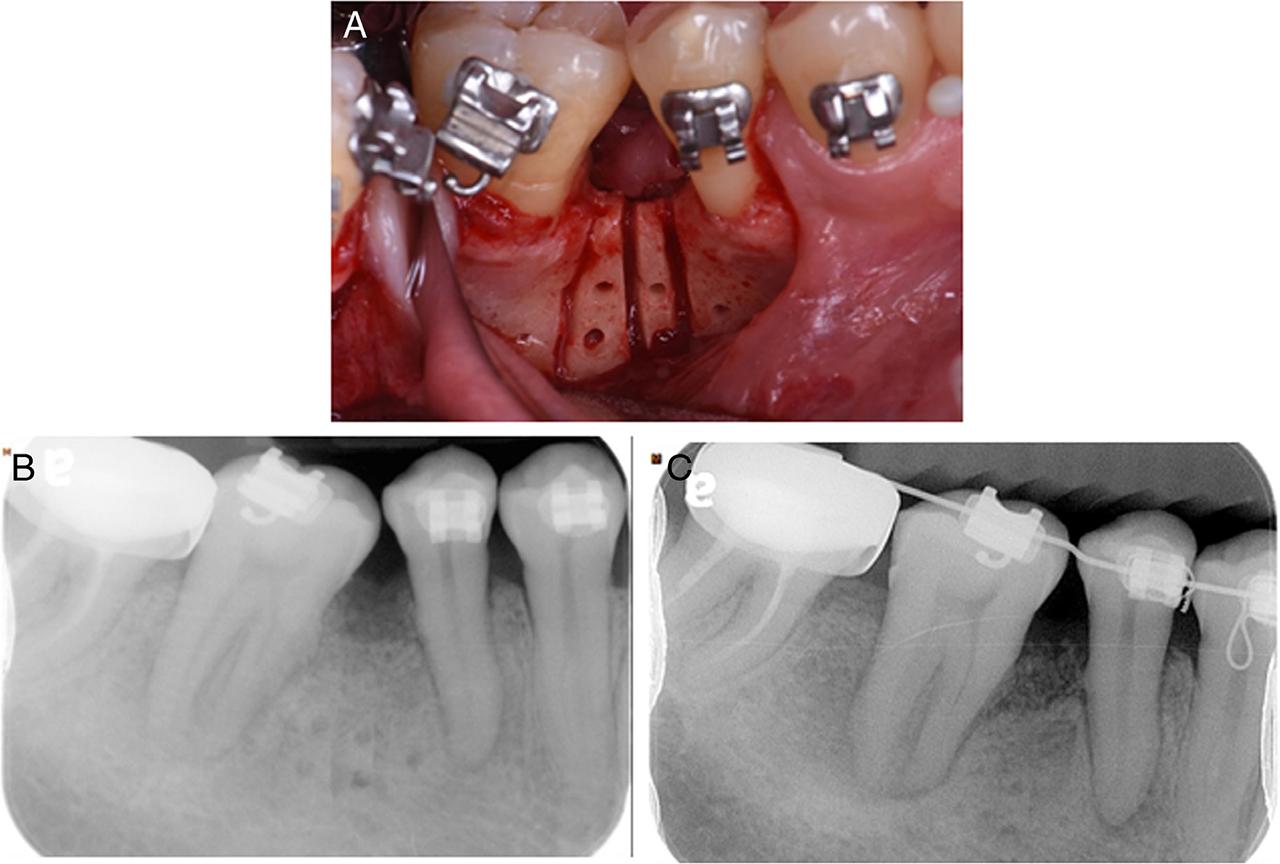

Because of the dimensions and characteristics of the bony defect of the mandibular left first molar, 8 months after the start of orthodontic treatment, guided bone regeneration (GBR) was attempted using a bone graft (Bio-Oss, Geistlich, Switzerland) and membrane (Bio-gide, Geistlich, Switzerland), combined with bone blocks (10 mm × 6 mm in dimension, harvested from the ramus on the distal side of the mandibular left third molar). After the graft, the bone thickness and height increased. To assist stabilisation, the bone fragments were temporarily fixed with tenting screws (Fig. 5). One month later, orthodontic movement commenced using a light continuous force and the mandibular second and third molars were uprighted using a V-bend in the arch wire.

Figure 5

Case 2: (A) The image shows the bone block temporarily fixed with tenting screws for stabilisation (Image shown here was from a similar intra-operative view to our patient's surgical procedure, courtesy of Dr. Chou). (B–E) Sequential panoramic radiographs of the lower left molars after GBR surgery.

Rather than a traditional corticotomy, the presented cases used piezoelectric tools for decortication because this approach is minimally invasive, more comfortable for the patient and therefore has greater acceptance.12,13 In Case 1, the PAOO procedure was adopted along with a FDBA allograft. Immediate orthodontic force for molar uprighting was applied without adverse consequences. The root movement was slow but continuous, taking 22 months for the molar root to move through the grafted ridge. In Case 2, a corticotomy was adopted along with an autogenous bone block via a xenograft and guided bone regeneration (GBR). The application of a protraction force was delayed for one month to avoid interfering with the resorbable collagen membrane and tenting screw stability. The space was closed smoothly at a rate of approximately 1 mm per month (Fig. 5B–E). The differences can be attributed to the patient's age, variation in the individual bone remodelling rate, and different graft materials.14,15 An autogenous bone graft, although associated with increased patient morbidity, possessed the ability to initiate osteogenesis and prompt bone remodelling, which might explain the space management efficiency in Case 2 after grafting.15 In Case 1, the mechanics of molar movement also involved root translation into the grafted area. Without A-P movement of the crown, the uprighting induced premature occlusal contact of the molar, which further impeded root movement.